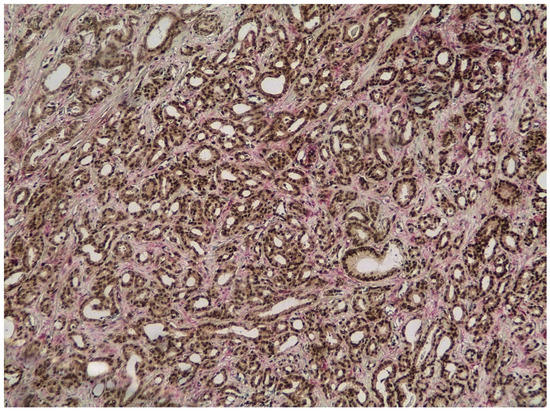

3.1. ERG and PTEN Associations in Prostate Carcinoma

| PTEN (Pca) | Score 0 | 68 | 50.7% |

| Score 1 | 56 | 41.8% | |

| Score 2 | 10 | 7.5% | |

| ERG (Pca) | Negative | 78 | 58.2% |

| Positive | 56 | 41.8% | |